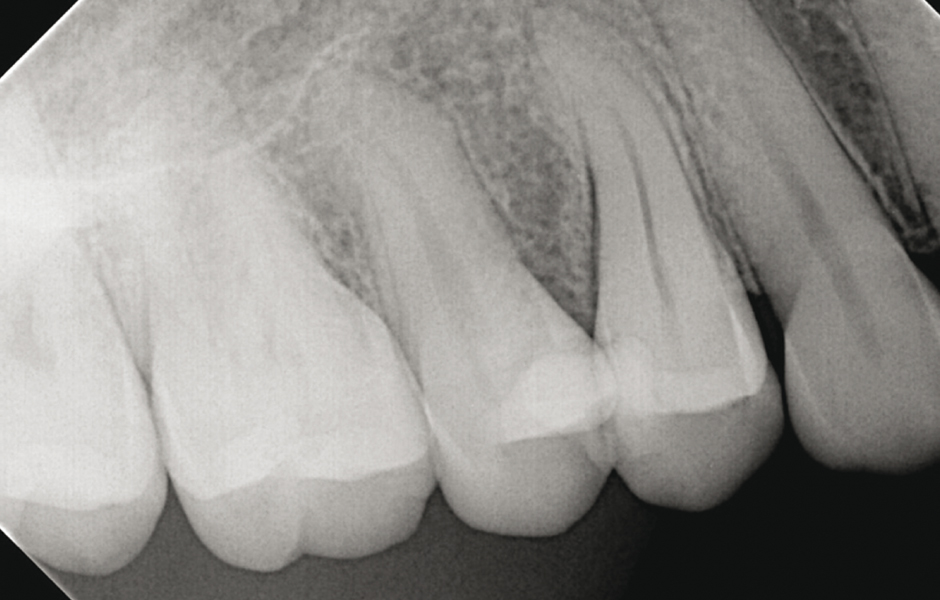

Vyšetřete měkké tkáně se zaměřením na otok či přítomnost píštěle, proveďte poklepové (perkusní) a palpační vyšetření a skusové testy na každém hrbolku. Ověřte stav pulpy pomocí chladového testu. Proveďte parodontální sondáž sulku a zaznamenejte případné úzké, izolované parodontální choboty. Nakonec zhotovte intraorální periapikální snímky a bite-wing snímky k posouzení periapikální oblasti a alveolární kosti. Na našem pracovišti rutinně využíváme CBCT k odhadu rozsahu praskliny apikálním směrem prostřednictvím nepřímých znaků. Lokalizovaná oblast ztráty kosti sledující povrch kořene nebo jediný úzký parodontální defekt může při nepřítomnosti generalizované parodontitidy svědčit pro přítomnost praskliny či fraktury (viz obr. 2a, b, c).⁴